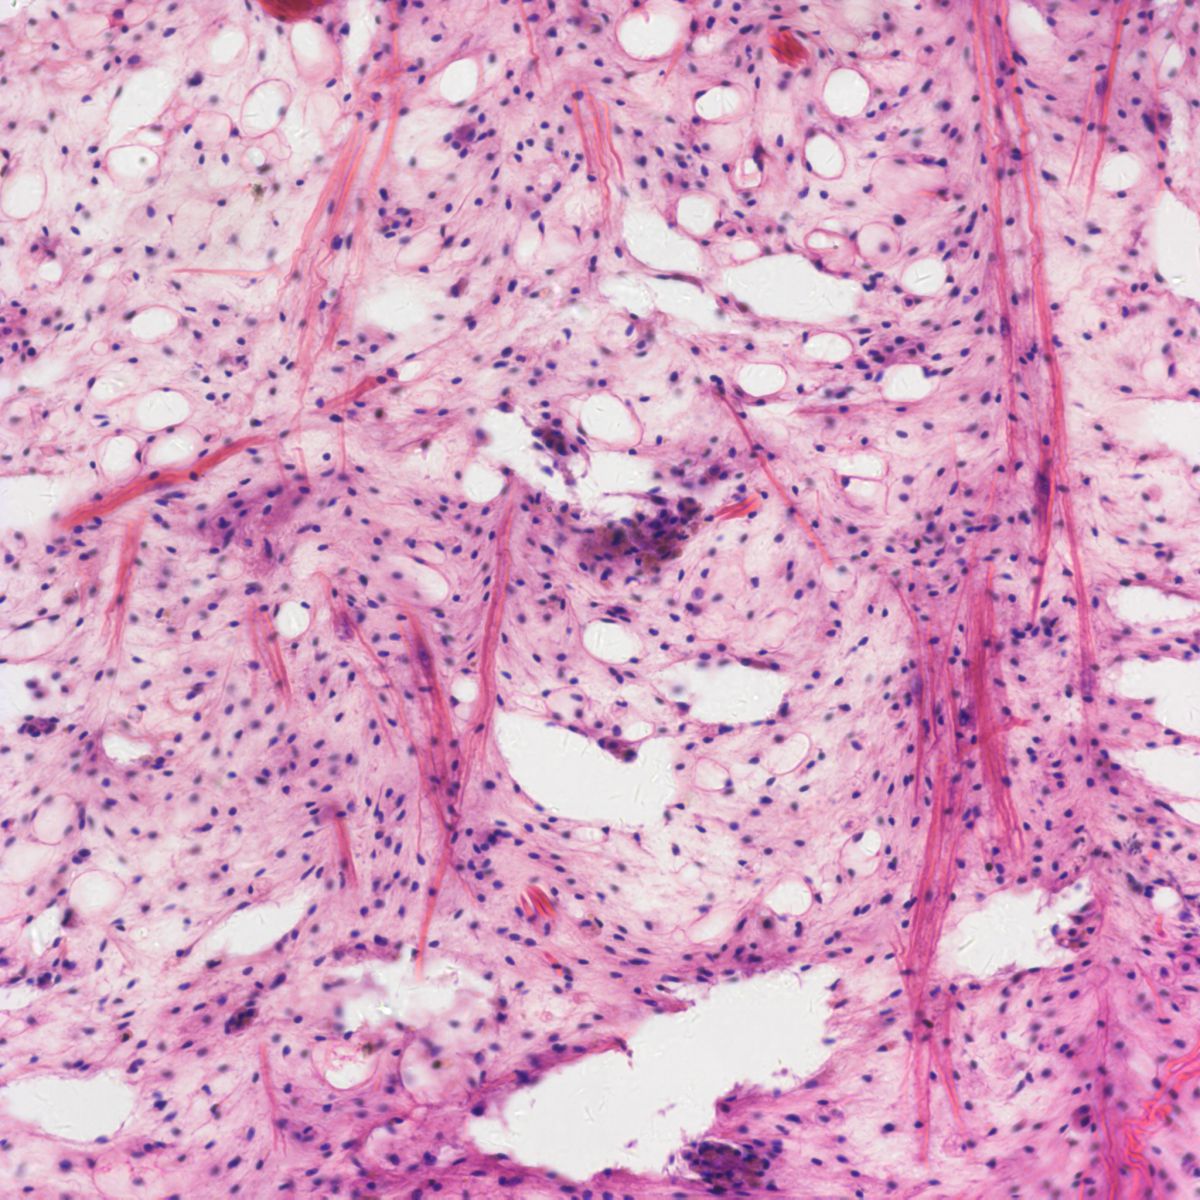

病理圖像分析對數碼成像的藍\紫\紅色提出了很高的要求,400DC在這些區域的完美表現,可以為病理分析判斷提供可靠的依據。